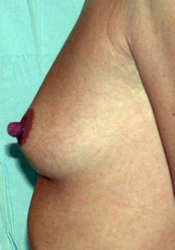

L’augmentation mammaire par pose d’implants est la seule alternative pour augmenter significativement et harmonieusement la taille des seins.

Les patientes de cet album ont des voies d’abord différentes, comme des tailles de prothèses ou de positionnement par rapport au muscle pectoral.